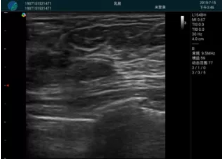

清晰顯示腺體內(nèi)低回聲快影,邊界清晰,包膜較光滑

確定進(jìn)針路徑并實(shí)時監(jiān)測抽吸針與腫塊位置關(guān)系

抽吸針進(jìn)入腫塊內(nèi)部進(jìn)行旋切

抽吸過程中可見腫塊明顯縮小,并根據(jù)腫塊位置改變針道位置

抽吸旋切后再進(jìn)行超聲復(fù)查,原腫塊區(qū)域未見殘留組織及出血